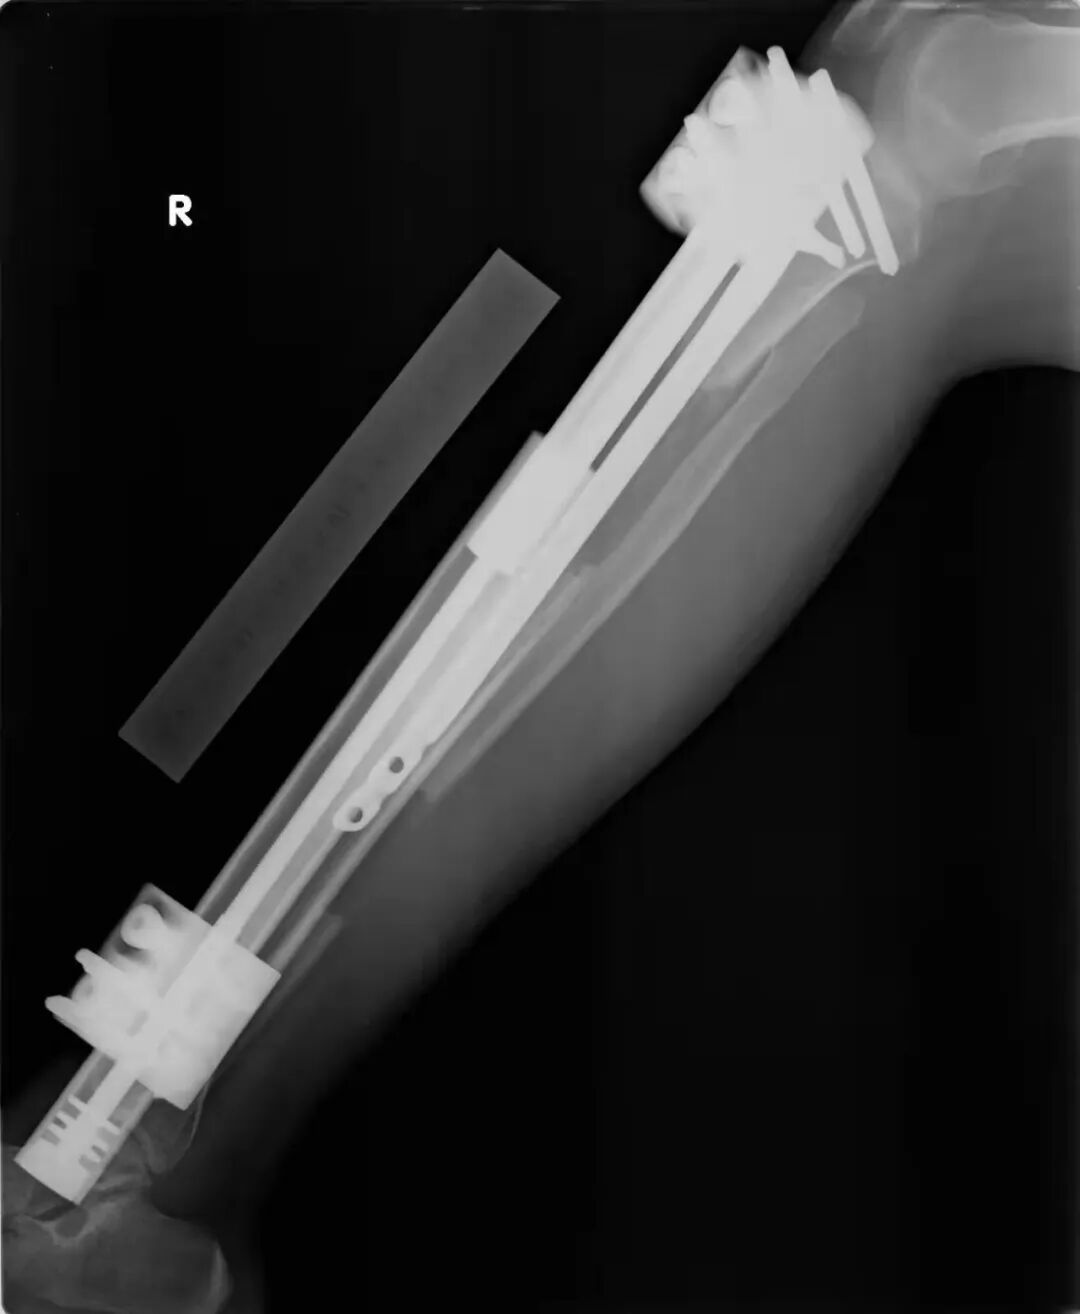

断骨增高术,简单来说,就是通过手术将人的腿骨锯断,然后再人为拉长断骨间的距离,达到增高的目的。上海市一家知名三甲医院的骨科主任医师张昊告诉《中国新闻周刊》,临床上医疗目的的肢体延长术,大多用的是髓内钉辅助外固定架延长(英文缩写LON)的方式,患者需经历不止一次手术。髓内钉是骨科手术中用于固定骨头的器械,是为了保证骨延长之后,腿不长歪。“手术技术是成熟的,但本身存在风险,而且出现并发症的概率很高。”他说。

程梦小腿的增高手术采用的便是LON方式。人体的下肢骨骼中,胫骨和腓骨两根长骨,组成了小腿的骨架结构,是腿部主要负重骨骼,肩负着行走和负重功能。2021年发表在《中华骨科杂志》上的一篇文章指出,LON方式的手术中,首先髓内钉被置入胫骨的中心,锁定髓内钉近端螺钉后,然后将胫骨、腓骨打断,并安装外固定架,术后通过调节外固定架,将两段骨骼的间隙拉得更开,使骨头沿髓内钉缓慢延长,完成目标延长长度后,锁定髓内钉远端螺钉,最后拆除外固定架。延长的骨头愈合良好后,需二次手术再去除髓内钉。